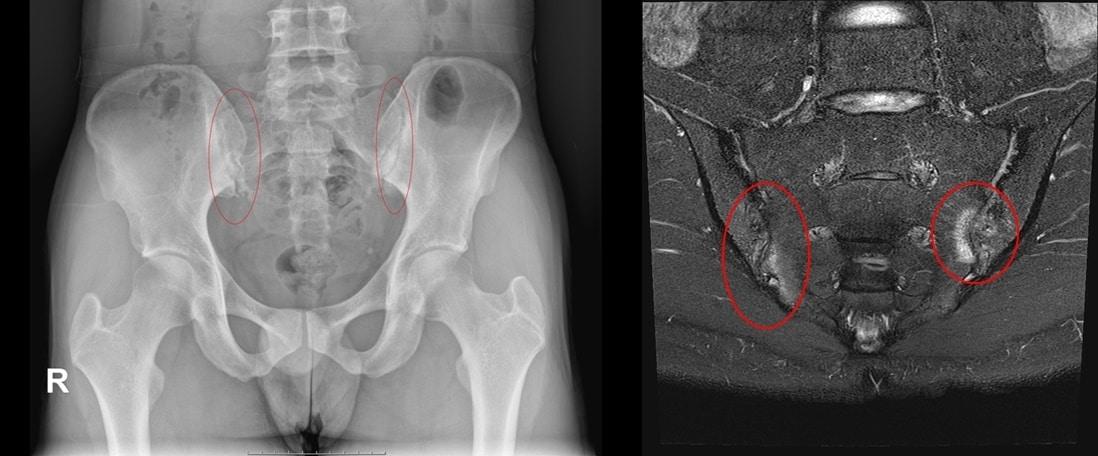

30·40대 허리통증, 방치하다 '대나무 척추' 된다